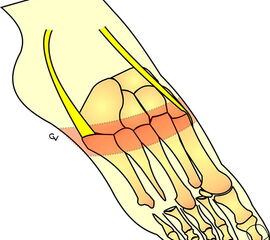

Amputationen am ersten Strahl

Amputationen innerhalb der Großzehe

Die bewährten Amputationslinien am 1. Strahl finden sich in Abb. 3.

Technik:

Exzision des Endglieds unter Bildung eines plantaren Lappens (Abb. 4). Die Absetzung kann im Endglied, im Endgelenk als Exartikulation oder im Grundglied distal der Ansätze der kurzen Beuger vorgenommen werden. Der Verschluss der Wunde durch Nähte ist wegen des längeren plantaren Lappens meist nur „mokassinartig“ möglich. Die Unregelmäßigkeiten werden im Verlauf der Wundheilung spontan ausgeglichen (Abb. 5).

Exartikulationen im Großzehengrundgelenk bedingen bei Neuropathie häufig Druckulze­rationen am Metatarsalekopf (Abb. 6, 7). Wenn vertretbar, wird die Basis des Grundglieds mit den Sehnensansätzen erhalten, um chronische Druckprobleme zu vermeiden (Abb. 8). Im Falle einer Exartikulation ist dem Druck unter dem Metatarsale-I-Kopf große Aufmerksamkeit zu widmen. Durch eine Entfernung der Sesambeine und Abtragen von plantaren knöchernen Prominenzen kann die Auflagefläche vergrößert und damit der Druck reduziert werden. Postoperativ muss der Mittelfuß durch Einlagen in seinem Gewölbe breitflächig abgestützt werden (Abb. 9). Ansonsten resultiert ein Plattfuß mit Pronation und Abduktion.